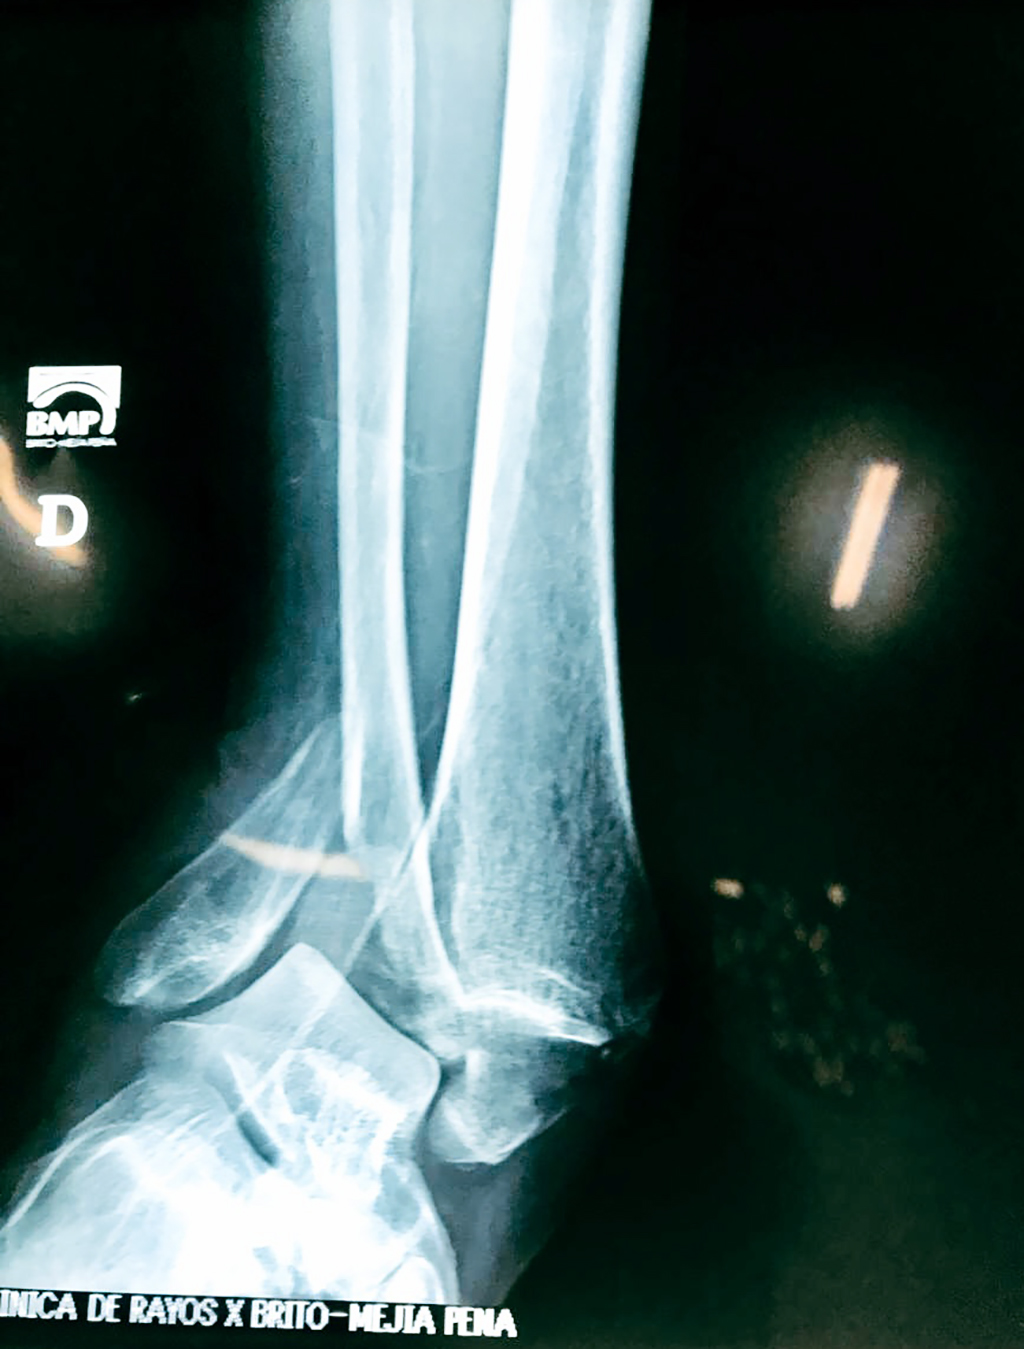

- Los extremos de los huesos están desalineados entre sí (desplazados).

- La fractura se extiende hasta la articulación del tobillo (fractura intra-articular).

- Los tendones o ligamentos (tejidos que sujetan los músculos y los huesos entre sí) están rotos.

Cuando se necesita cirugía, es probable que esta implique el uso de clavijas de metal, tornillos o placas para sostener los huesos en su lugar mientras la fractura se consolida. Los elementos de soporte pueden ser temporales o permanentes.